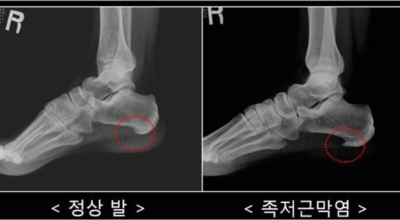

족저 근막염이란?

족저 근막이란 발가락 시작지점부터 발뒤꿈치뼈까지 발바닥 전체를 감싸고 있는 두꺼운 막을 말해요. 족저 근막은 발바닥 아치를 보존시켜 발바닥이 지면을 내딛음으로써 생기는 쇼크을 흡수하는 중요시되는 역할을 수행하고 있어요. 이 족저 근막에 일차적으로 서서히 조직 훼손이 일어나고 계속적인 활동에 의하여 염증이 커지면서 발 뒤꿈치 부근 통증을 일으키게 되는데 염증은 무리하고 반복적인 동작, 많은 활용으로 마찰에 의해 발생해요.

족저 근막염은 염증에 의한 훼손 및 통증을 유발하는 질환인데요 족저 근막염 증상은 동일한 발뒤꿈치 통증 하글런드 병변의 기형으로 알려져 있으고 아킬레스 건과 연관이 깊다고 해요. 특히 근육이 덜 풀린 아침 시간 대는 보행 시 날카롭고 바늘로 찌르는 듯한 심한 통증을 느끼게 된다고 해요. 하지만 아침 시간 대를 지나 오후에 접어들면서 일정 양 통증은 서서히 감소하기 시작한다고 하는데요 초기 증상이 나타난다면 필수로 전문의를 찾아 조기치료하는 것이 바람직해요.